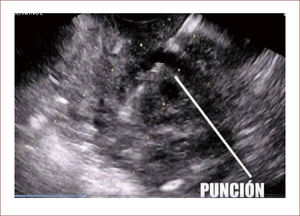

Con el EUS esto ha cambiado ya que sin importar el tamaño del quiste y su impresión o no sobre la pared gástrica o duodenal, se pueden ver. Por lo tanto, se pueden puncionar y hacer drenajes dirigidos 25. Además es importante el hecho de que el EUS muestra si hay vasos sanguíneos que están entre la pared y el sitio de drenaje, evitando estos sitios y de esta manera, una de las complicaciones del procedimiento que es la hemorragia. Por medio de este método se pueden colocar stent de diferentes tamaños 25. Nuestro grupo realiza el abordaje con EUS de todos los seudoquistes que son para drenaje. Por medio de este método seguimos una secuencia que es:

-EUS diagnóstica: en esta se mide el tamaño del quiste, se caracteriza su contenido, se determina si hay vasos interpuestos entre la pared y el quiste, mide el tamaño de la pared, siendo importante que éste esté entre 5 y 10mm (pared apta para drenaje).

-Se decide drenar, se activa del EUS el vector de drenaje que permite dirigir la aguja y punciona el quiste.

La punción se hace con una aguja 19G. Esta permite pasar así una guía hidrófilica dentro del quiste. Esta maniobra abre el espacio para poder introducir diferentes aditamentos técnicos por medio de la guía.

-En esta técnica se han usado cistotomos (Instrumento que va por la guía y tiene una oliva metálica que trasmite energía y corte por medio de la unidad electro quirúrgica), o papilótomos de punta que tienen un hilo metálico al final que cumple la misma función. Así se puede abrir un orificio entre la pared gástrica o duodenal y el quiste.

-Elaborado el orificio se pasa un balón de dilatación biliar de 6mm y se dilata el trayecto.

-Luego se pone un stent, este puede ser de teflón o plástico, pero estos se ocluyen fácilmente, por lo que se prefiere un stent autoexpandible biliar de 10mm recubierto. El stent al quedar en su sitio permite el drenaje del material del quiste y los lavados diarios por medio de aditamentos como balones de oclusión biliar que se inflan dentro del stent, para pasar líquido por medio de ellos, desinflando luego y aspirando.